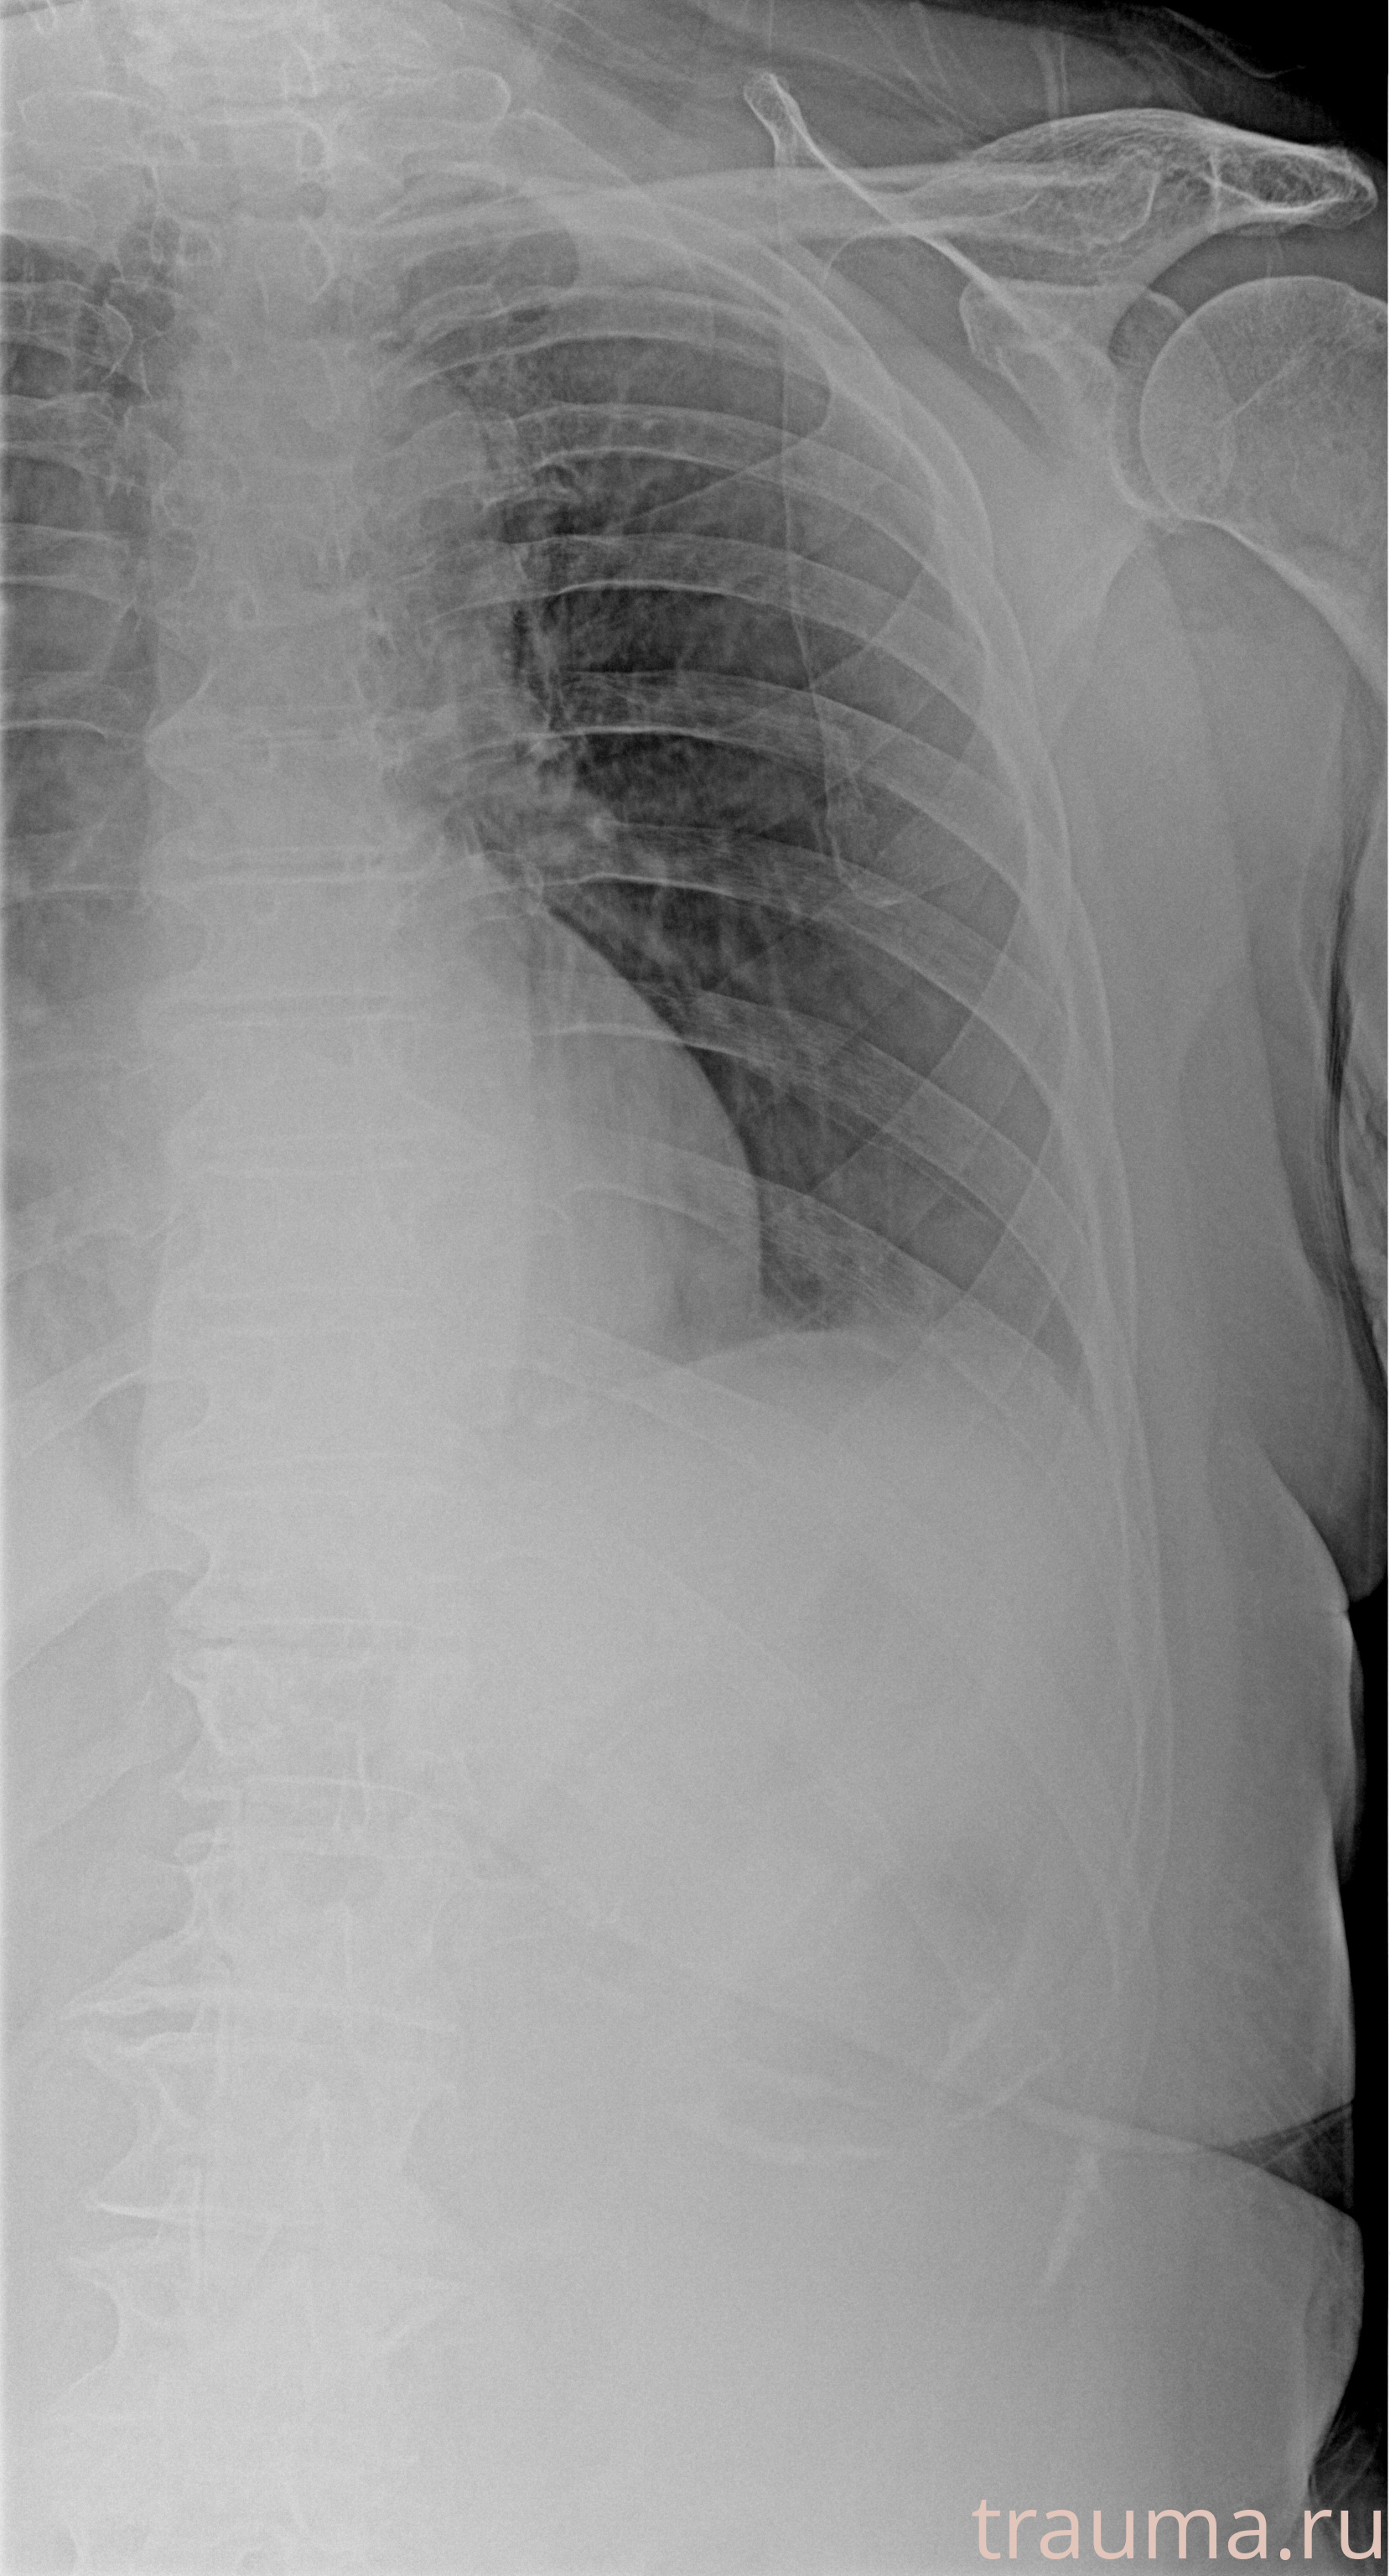

Рентгенограммы

Рентген на дому: по вашему адресу приезжает врач-рентгенолог, травматолог-ортопед с мобильным рентгеновским аппаратом, проводит диагностику травмы или заболевания, делает необходимые рентгенограммы, дает рекомендации по дальнейшему лечению. Получить качественные снимки в домашних условиях возможно благодаря уникальной методике, разработанной МосРентген Центром для института  Склифосовского

при переломе шейки бедра и пневмонии от компании МосРентген Центр - партнера Института имени Склифосовского